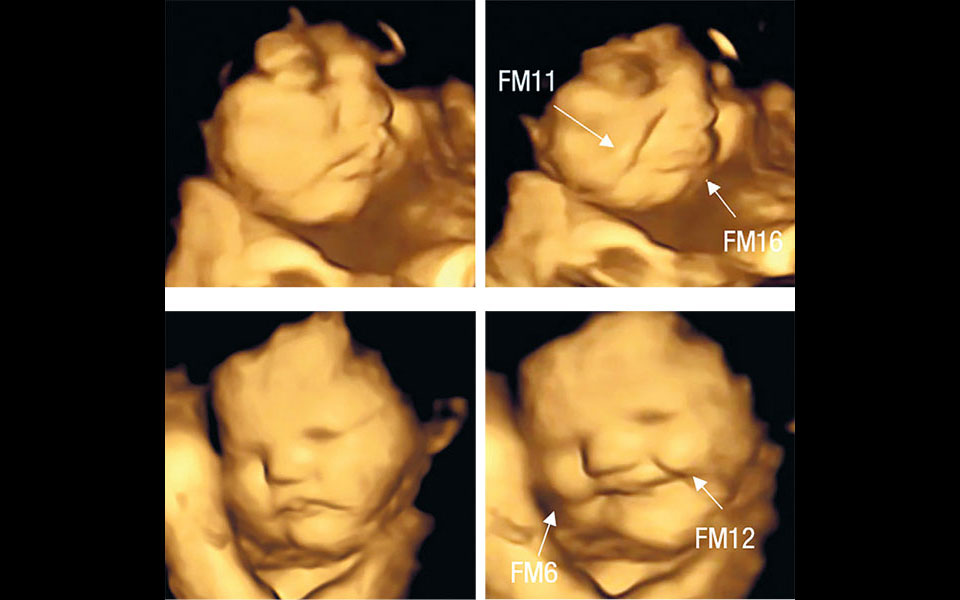

Οι ερευνητές του βρετανικού πανεπιστημίου έλαβαν τρισδιάστατες υπερηχογραφικές απεικονίσεις από 110 εγκύους, ηλικίας 18 έως 40 ετών, που βρίσκονταν στην 32η και 36η εβδομάδα της εγκυμοσύνης τους. Οι εξετάσεις πραγματοποιήθηκαν περίπου 20 λεπτά αφού οι γυναίκες είχαν καταναλώσει ταμπλέτες που περιείχαν σκόνη καρότου ή λαχανίδας (κέιλ), ενώ τους είχε ζητηθεί να μην καταναλώσουν οτιδήποτε άλλο τουλάχιστον μία ώρα πριν από την εξέταση.

Αναλύοντας τις εικόνες, οι ερευνητές είδαν ότι τα έμβρυα, οι μητέρες των οποίων είχαν φάει καρότο, έμοιαζαν να χαμογελούν ευχαριστημένα. Αντιθέτως τα έμβρυα των γυναικών που είχαν καταναλώσει τα χάπια λαχανίδας έμοιαζαν να κλαίνε ή τουλάχιστον να κάνουν μορφασμούς δυσαρέσκειας. Συγκρίνοντας τα υπερηχογραφήματα με αυτά που έλαβαν από μία ομάδα ελέγχου στην οποία οι γυναίκες δεν είχαν καταναλώσει τρόφιμα, οι ερευνητές κατέληξαν ότι η πρόσληψη κάποιας γεύσης από την έγκυο αρκούσε για να πυροδοτήσει την αντίδραση του εμβρύου.